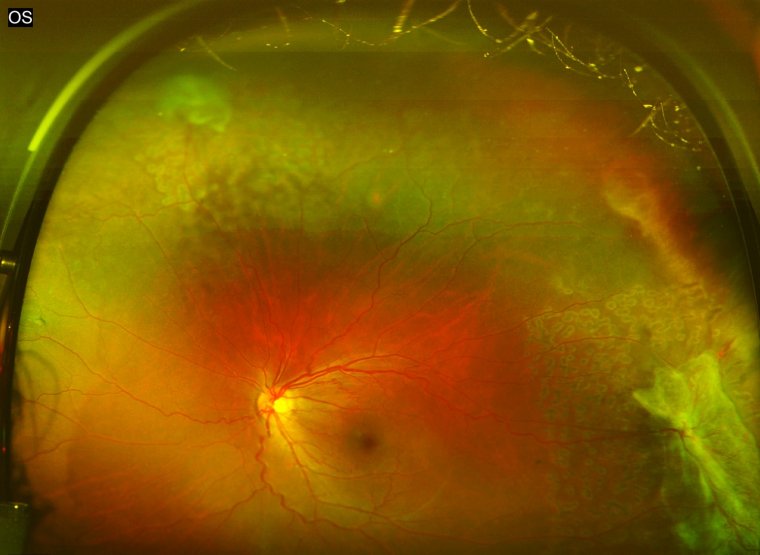

Sickle cell retinopathy is a vision-threatening complication that arises from sickle cell disease, a genetic disorder that affects red blood cells. In individuals with sickle cell disease, the red blood cells become abnormally shaped, resembling a crescent or sickle. These misshapen cells can obstruct blood vessels, leading to a variety of complications, including those that impact the retina – the light-sensitive tissue at the back of the eye.

Sickle cell retinopathy occurs when the blood vessels supplying the retina become blocked, leading to insufficient oxygen delivery and subsequent damage to the retinal tissue. Over time, this damage can impair vision and, in severe cases, even result in blindness. Sickle cell retinopathy is a progressive condition that can manifest in various stages, ranging from mild retinal changes to more severe complications such as retinal detachment.

Sickle cell retinopathy can present in various forms and severity levels. The Goldberg classification system is widely used to categorize the condition into five distinct stages, each reflecting the progression and severity of the disease: